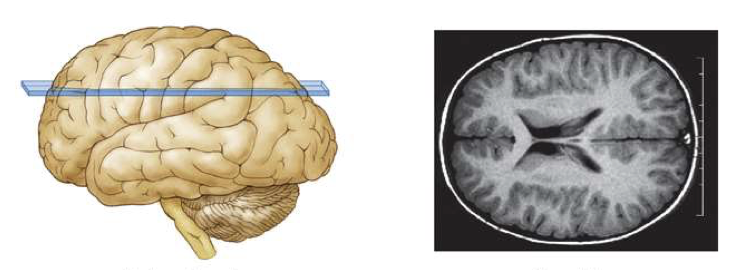

What is this brain plane called?

What is this brain plane called?

horizontal section

A top-down cut showing the brain from above

like slicing a hamburger bun